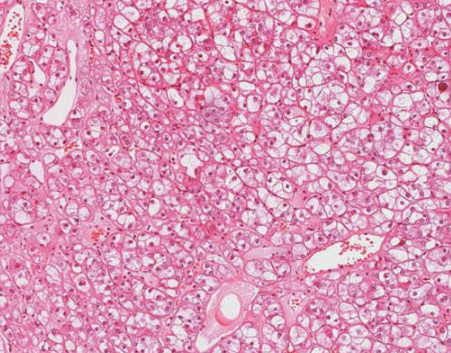

肾嫌色细胞癌是一种非常见的肾细胞恶性肿瘤,但与普通的肾细胞恶性肿瘤相比,它的恶性程度相对较低,它的形态比较特殊,恶性程度不高,根据临床医学认识,它起源于肾集合管上皮,目前在治疗此类恶性肿瘤时,大多会进行根治性切除。

全肾脏切除后往往预后效果好,与同期其他类型的恶性肿瘤相比,它的5年生存期比例相对较大。

对于患者来说,做到早发现早治疗相当重要。它的早期症状相对较少,但是肿瘤增大后可以出现明显的血尿、持续性腰痛,同时多伴有腹部包块,以上症状也被临床医学上称之为肾癌的三联征,若出现以上症状要引起重视。